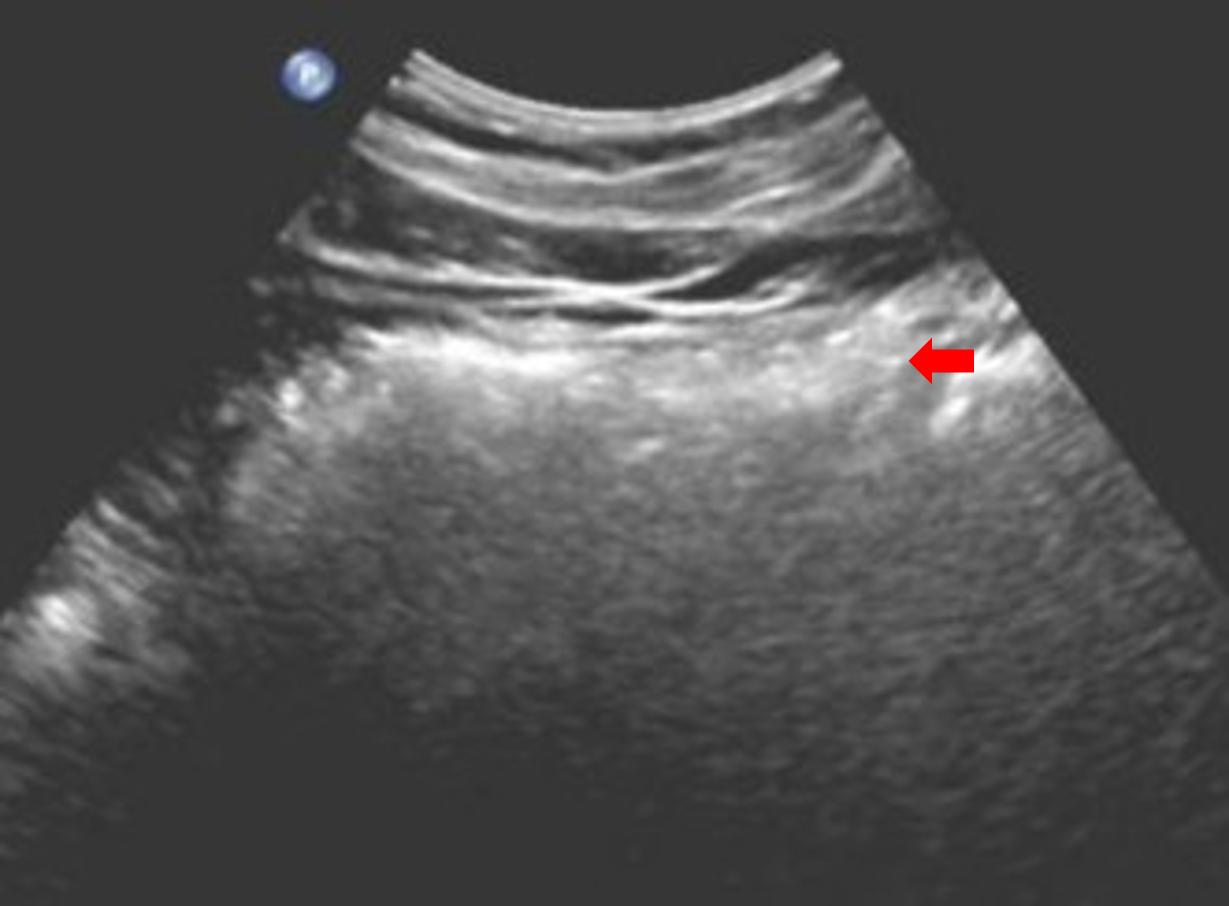

对于腹彩超声医生来说,最大的敌人可能就是胃肠道内的气体了,超声照射在气体上,会形成一团白白亮亮的“高回声”,这像云朵的一团“高回声”遮挡住了后方的器官,无法显示出来。所以对于一些餐后的患者,由于胃内的食物残渣和气体的遮挡,后面的胰腺很多时候就无法显示。

图一,餐后的上腹部,中间这团白白的亮亮的“云朵”就是气体,后面的脏器被气体的“光芒”所遮挡,完全无法显示,这个时候患者有胰腺炎,胰腺的肿瘤,就无法显示出来了。